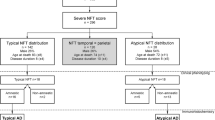

Patients were evaluated at the Penn Frontotemporal Degeneration Center (FTDC) or Alzheimer’s Disease Research Center (ADRC) and followed to autopsy at the Penn Center for Neurodegenerative Disease Research (CNDR) as part of ongoing and previous clinical research programs. Patients included in the study were selected from Penn Integrated Neurodegenerative Disease Database (INDD) and had autopsy-confirmed primary diagnosis of ADNC. Patients were classified as non-amnestic (naAD) based on clinical criteria for non-amnestic syndromes designated prospectively using review of standardized clinical assessments at weekly diagnostic consensus meetings at the FTDC or ADRC, including PPA variants [21], bvFTD [46], PCA [11], and CBS [3]. In legacy autopsy samples clinically evaluated prior to modern criteria a retrospective chart review was performed by experienced investigators (SA, KC, JP, DJI) to confirm non-amnestic presentation and clinical phenotype. A similar cohort of patients with amnestic AD (aAD) were selected who met clinical criteria for AD [33] with primary neuropathological diagnosis of ADNC and did not meet exclusion criteria below.

Cases with clinically relevant pathological comorbidities of transitional/limbic or diffuse/neocortical Lewy bodies, hippocampal sclerosis, cerebrovascular disease, or previous structural brain disease were excluded from the cohort, along with those with damaged or missing hippocampal tissue. Mild levels of age-related alpha-synuclein and/or TDP-43 pathology in limbic regions (i.e., brainstem-only or amygdala-only stage Lewy body [30], limbic-predominant age-related TDP-43 encephalopathy) [39] were included. Clinical demographics, mini-mental state examination (MMSE) score closest to death, neuropathological diagnosis data, and ApoE status were obtained from INDD. Our final cohort is summarized in (Table 1).

Using this base model, we first examined tau distribution across hippocampal subfields sampled, where the fixed factor region had strata for each subfield (i.e., DG, CA4, CA3, CA2, CA1, Subiculum, and ERC). DG was selected as the reference category to assess the hippocampal distributions, while the interaction term of clinical group x region tested divergent regional distributions of tau pathology between clinical groups of AD (i.e., naAD vs aAD) (Online Resource 1, Supplementary Table 2).

In a separate model we tested regional differences between clinical subgroups of naAD in comparison to aAD (i.e. bvFTD vs aAD, CBS vs aAD, and PPA vs aAD) while adjusting for covariates mentioned above. Cases with a clinical diagnosis of PCA were excluded from our clinical subgroup analysis due to the low number of patients in this group (N = 2) (Online Resource 1, Supplementary Table 3).

Next, we examined the relative distribution of tau in the neocortex with the fixed factor region stratified by cortical regions sampled (i.e., SMTC, MFC, ANG) and included hippocampus CA1 as the reference region. We included the same demographic covariates as above, and our main outcome was the clinical group x region interaction (Online Resource 1, Supplementary Table 4). Similarly, a separate model tested for regional differences between clinical subgroups of naAD in comparison to aAD (i.e., bvFTD vs aAD, CBS vs aAD, and PPA vs aAD) while adjusting for covariates as above (Online Resource 1, Supplementary Table 5).

Finally, to test the relative distribution of tau between groups, we averaged the raw %AO for the 3 cortical regions sampled (i.e. neocortical average %AO) and calculated a ratio of neocortical average %AO/CA1%AO for each marker in each individual patient and used Welch two sample t-tests to compare the clinical groups. All statistical analyses were performed using version 4.1.1 R statistical software and two-tailed statistics with a significance level of p < 0.05.

Demographics and clinical features

Patients in the naAD group presented at younger ages compared to aAD (p = 0.02). In addition, the aAD group had a significantly older age at death compared to naAD (p = 0.003), while there was no difference in disease duration between the two groups (p = 0.25). Two groups had relatively similar ANDC “ABC” score stages [36]; nearly all patients had Braak stage V or VI (Table 1).

Lewy body co-pathology was seen at a higher rate in the aAD group (57.5%) compared to the naAD (31%) (p = 0.03). In the aAD group, 37.5% of cases had limbic TDP-43 co-pathology, whereas 18% of patients with naAD showed evidence of TDP-43 proteinopathy at autopsy (p = 0.09). The distribution of phenotypic variants in pathological groups is also shown in (Table 1). There was similar level of global cognitive impairment closest to death in both aAD and naAD groups (p = 0.82). The rate of patients with at least one copy of APOE ε4 allele was higher among the aAD patients (72.5%) compared to the naAD group (41%) (p = 0.009).